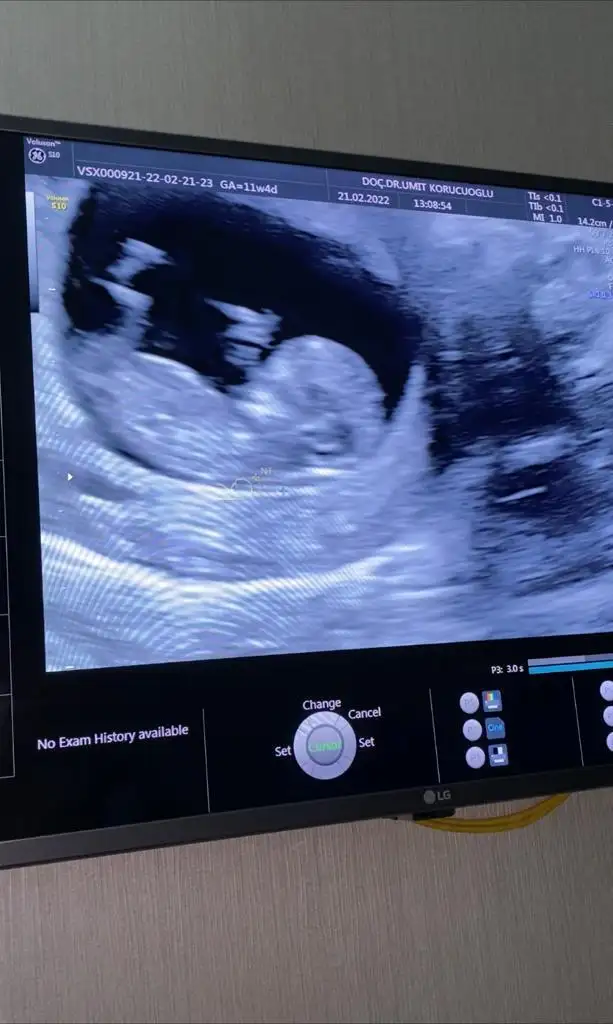

Eki Görüntüle 3011205 Eki Görüntüle 3011204 Eki Görüntüle 3011205 Eki Görüntüle 3011206 Eki Görüntüle 3011206Bende tam onu diyecektim canimsakıncası yoksa usg fotosunu paylaşır mısınız kızlar çok sevindim güzel haberler almanıza darısı bize sanırım ikili testi bende yaptırmayacağım bu sefer riskli olsa ne olacak hersey Allahtan

Ay erkek gibi hissettim benkızlar fotoğrafları yüklemeyi beceremedim pek kusura bakmayın. cinsiyet tahmini olan var mı